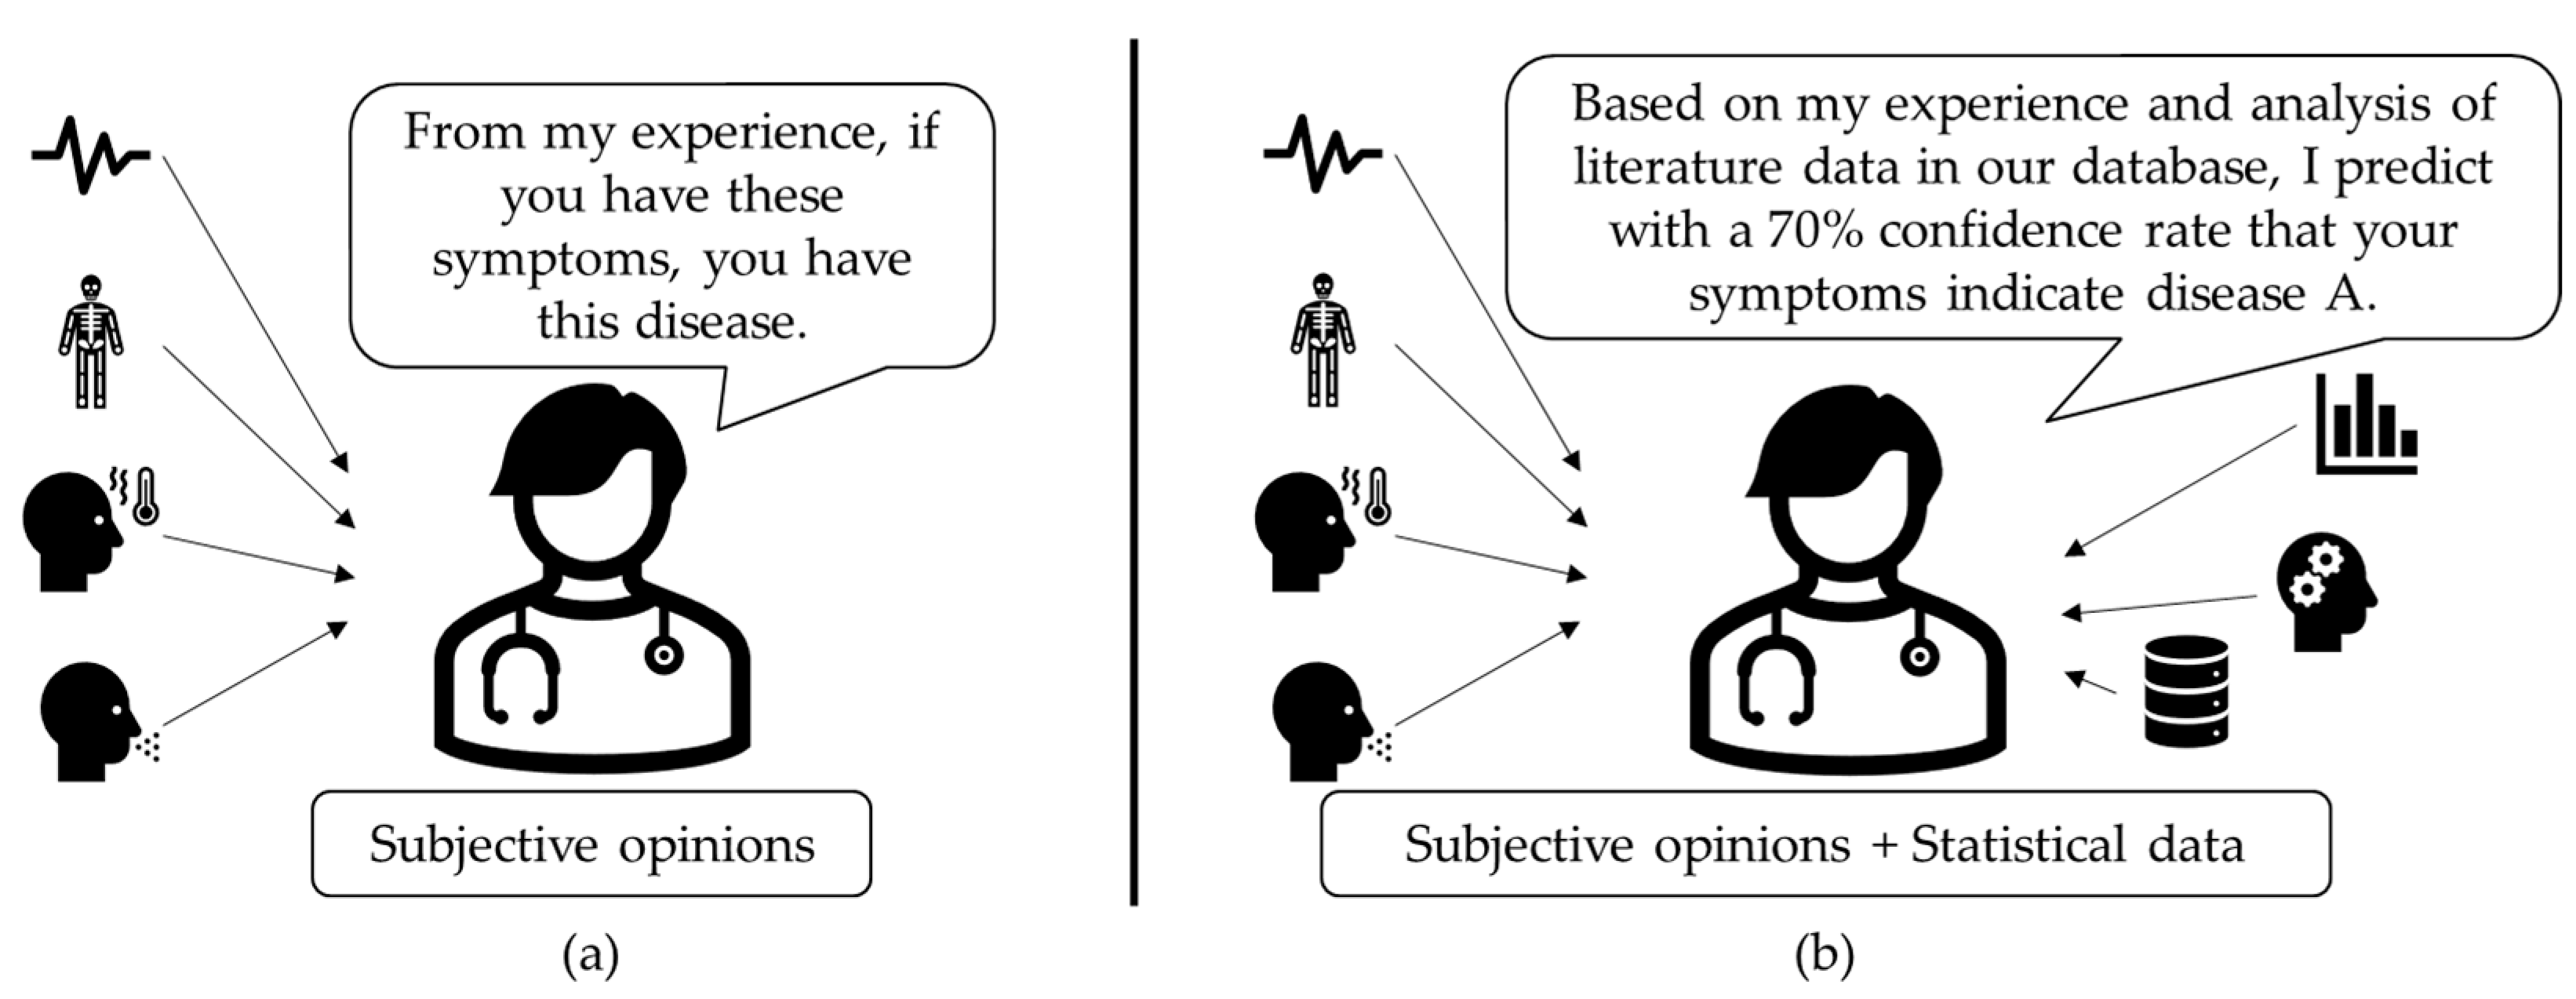

:1. Introduction

1.1. Background Knowledge